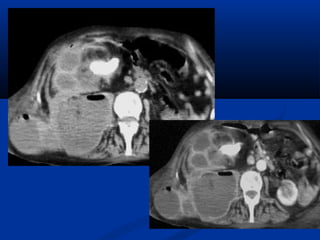

khí thuûngkhí thuûng

- Nhieãm truøng nhu moâ thaän ít gaëpNhieãm truøng nhu moâ thaän ít gaëp

nhöng ñe doaï tính maïng, vôùi ñaëcnhöng ñe doaï tính maïng, vôùi ñaëc

ñieåm taïo khí.ñieåm taïo khí.

- Öu theá phuï nöõ (2:1) vaø ngöôøi tieåuÖu theá phuï nöõ (2:1) vaø ngöôøi tieåu

ñöôøngñöôøng

- 62 – 70% do62 – 70% do E. ColiE. Coli

- Laâm saøng naëng: soát, ñau vuøngLaâm saøng naëng: soát, ñau vuøng

hoâng, taêng ñöôøng huyeát, nhieãmhoâng, taêng ñöôøng huyeát, nhieãm

toan, maát nöôùc vaø roái loaïn ñieäntoan, maát nöôùc vaø roái loaïn ñieän

giaûi.giaûi.

Vieâm thaän – beå thaänVieâm thaän – beå thaän

2 loaïi:2 loaïi:

(1) Phaù huûy nhu moâ thaän keøm hieän dieän khí(1) Phaù huûy nhu moâ thaän keøm hieän dieän khí

daïng veät daøi hay loám ñoám, tuû vong 69%.daïng veät daøi hay loám ñoám, tuû vong 69%.

Ñieàu trò baèng caét boû thaän khaån caápÑieàu trò baèng caét boû thaän khaån caáp

(2) Ñaëc tröng laø tuï(2) Ñaëc tröng laø tuï

dòch taïi hoaëc quanhdòch taïi hoaëc quanh

thaän keøm caùcthaän keøm caùc

boùng khí trong heäboùng khí trong heä

thu thaäp, töû vongthu thaäp, töû vong

18%. Ñieàu trò baèng18%. Ñieàu trò baèng

daãn löu qua da.daãn löu qua da.